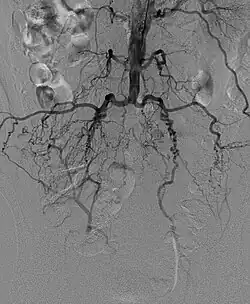

Leriche-Syndrom in der Angiographie (Katheter vom Arm in die Bauchaorta). Die Beine werden über Kollateralen aus den Lumbalarterien versorgt.

Das Leriche-Syndrom (benannt nach dem französischen Chirurgen René Leriche) ist ein kompletter Verschluss der Aorta distal des Abganges der Nierenarterien, meist vor der Bifurkation in die Beckenarterien. Die Ursachen dafür können Arterienverkalkung (Arteriosklerose), Arterienwandentzündungen (Vaskulitis) sowie Blutgerinnsel (Thrombose/Embolie) sein. In allen Fällen kommt es zu einer Verengung auf der Höhe der Aufzweigung der Bauchschlagader in die Becken-Arterien. Je nachdem, ob die Durchblutungsstörung plötzlich auftritt oder sich langsam entwickelt, kommt es zu kalten Beinen, Schmerzen, erektiler Dysfunktion (Impotenz) und Muskelschwund.